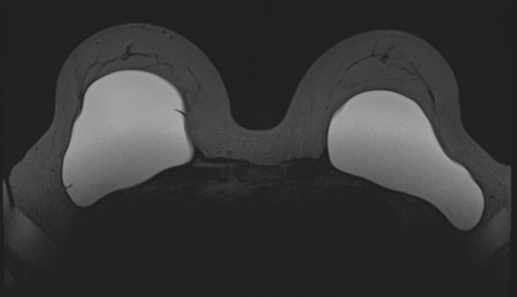

Een MRI van uw borstimplantaten is een medisch beeldvormend onderzoek dat specifiek kijkt naar de staat van uw borstprotheses. Een MRI scan geeft een duidelijk beeld of er sprake is van een scheur, lekkage of slijtage van een implantaat. Bij MRI Centrum kunt u terecht voor een MRI borstimplantaten, ook zonder verwijzing van uw huisarts. U betaalt het onderzoek dan zelf.

Uw borsten hangen vrij in een speciale borstcoil. U kunt dit vergelijken met een soort kussen met twee uitsparingen voor uw borsten.

De MRI richt zich specifiek op de borstimplantaten. Wanneer u naast de borstprothesen óók de gezondheid van uw borsten wilt laten onderzoeken, dan is daar een aanvullend onderzoek voor nodig, we bieden dat in een combinatieonderzoek.